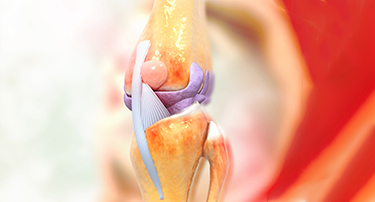

Everything You Need to Know About Joint Replacement Surgery

Patients with severe end-stage joint disease are often advised to undergo joint replacement surgery. Osteoarthritis, rheumatoid arthritis, other inflammatory joint issues, a history of joint traumas, fractures, joint infections

From Diagnosis To Recovery: A Comprehensive Guide To Orthopedic Health

Orthopedic health is critical to our ability to move, our ability to perform daily activities, and our ability to remain pain-free.

The Future Of Joint Replacement: What Patients Need To Know

Joint pain can literally cripple a person's ability to move, work, or live. Whether caused by arthritis, trauma, or wear and tear, joint replacement surgery is providing hope and mobility for millions of individuals across the globe.